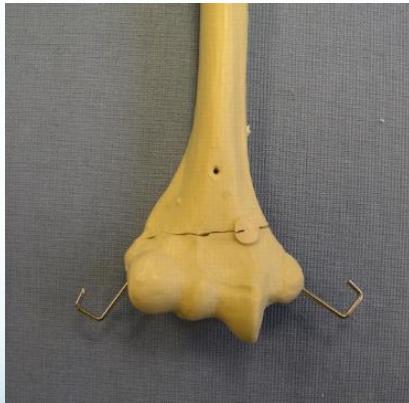

Lateral Condyle - Humerus

- Mostly cartilaginous

- Intra-articular fracture

- Fracture easily missed

- Displacement not appreciated/underestimated

- Needs fixation even if undisplaced

- Treatment: reduction, K-wire, slab

- If not fixed, may displace